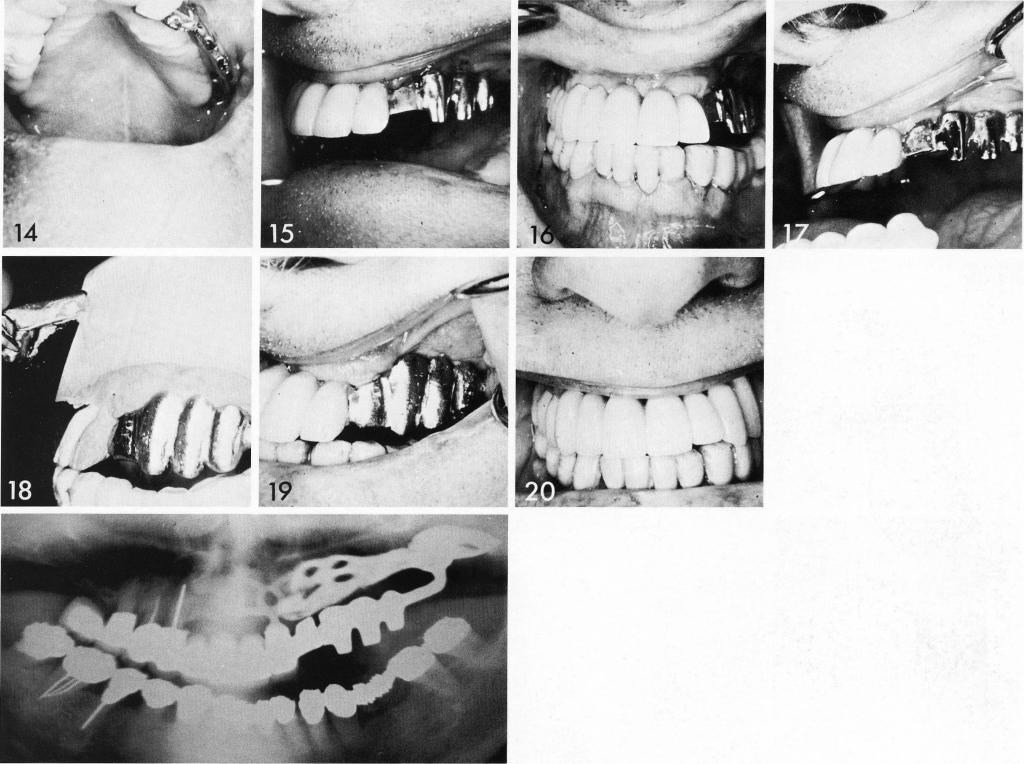

The patient had been fitted with a bulky partial that attached to, and threatened the security of, his remaining teeth (I). A universal type bladevent was inserted in the cuspid area (2,3). The endosteal and artificial abutments were included in a restoration bearing a cantilevered female attachment (4). An impression was taken for the unilateral pterygoid extension implant (5), and the site closed (6). The restoration for the endosteal abutments and the pterygoid extension implant compliment one another (7,8). The restoration was cemented (9-11), and the pterygoid extension implant inserted (12 through 17). The implant included a palatal portion as additional support because of the large span. When the tissues healed, the final portion of the splint was fabricated and the case finished.

1 The maxillary pterygoid extension implant inserted